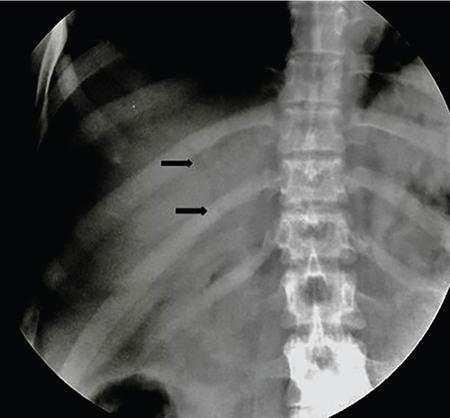

Samarjit Ghuman, Seema Sud, Deeksha Rastogi, Swapnil Sheth, T.B.S. Buxi PLAIN RADIOGRAPHY FOR HEPATOBILIARY IMAGING The diagnostic imaging techniques for hepatobiliary imaging can be intimidating with many techniques/modalities providing the information desired. The job of the diagnostic radiologist includes being familiar with the available choices and pick the ‘best fit’ keeping in mind the pros and cons of each modality, which includes plain X rays, Contrast studies using plain X rays and fluoroscopy, Ultrasound includiojng Doppler and Ultrasound elsastography, CT including multiphase CT and MRI and MRI elastography. Understanding the strengths and weaknesses of every modality as well as the ability to tailor each study individually will help to optimise patient cares. The abdominal radiograph is performed almost exclusively in the supine position and in the AP (anteroposterior) projection. In case of acute abdomen, an erect chest radiograph should also be performed to look for free air under the diaphragm. The standard abdominal radiograph should extend from the diaphragm to the inferior pubic rami, and includes the lateral abdominal wall musculature. Routinely no preparation is required for abdomen radiograph done for hepatobiliary imaging. The radiograph has limited soft-tissue contrast, however, the liver being the largest intra-abdominal organ, casts a perceptible shadow. The margins of the liver can indirectly be seen by outline of adjacent organs like lung, hemidiaphragm, pro-peritoneal fat line, kidney and gas shadows of stomach/colon. The right lobe is seen better than the left lobe of liver. The following pathologies may be visualized on the plain radiograph of the liver. Liver enlargement Liver mass Calcification Increased radiodensity of the liver Decreased radiodensity of the liver An ultrasound is the first line investigation; however, a radiograph may be done for routine evaluation of abdominal pain. The following pathologies may be seen on plain radiograph of the biliary tree. Calculi and Calcifications Gas ULTRASOUND OF HEPATOBILIARY SYSTEM Ultrasonography (USG) is the initial imaging modality of choice for scanning hepatobiliary system. USG is accurate and has high sensitivity and specificity in diagnosing biliary pathologies. Table 9.1.1 shows indications of ultrasound in hepatobiliary system. The real-time nature of ultrasound lends itself to demonstrate mobility of calculi and sludge and the sonographic Murphy sign can easily be elicited during scanning. The main disadvantage is operator dependence, patient’s body habitus, presence of gas which can obscure the visualization of organs, overlying bandages in a postoperative patient and incomplete evaluation in a nonfasting state. USG of upper abdomen should be done after 6–8 hours of overnight fasting. Milk and fatty food should be avoided as they cause contraction of the GB and may cause the GB walls to appear thickened. History of previous surgery, especially cholecystectomy should be elicited. The patient may be positioned in supine or left lateral decubitus position. The GB can be scanned from a high/lateral view, looking through the ribs in supine position or through a sub-costal view in left lateral decubitus position. Position of patient may be changed to demonstrate mobility of structures. The GB is an anechoic structure which is located in the GB fossa along the posterior and inferior aspect of the liver. It has a fundus, body and a neck. It should always be examined in at least two planes (Fig. 9.1.6A and B). The wall of the normal GB should measure 3 mm or less and pathological GB wall thickening can be due to cholecystitis or a neoplastic aetiology. Calculi appear as mobile hyperechoic foci, with distal acoustic shadowing. Other pathologies include polyps and sludge which can be differentiated on the basis of their mobility. The CBD measures less than 6 mm in diameter with increase in the diameter with patient’s age and after cholecystectomy. The CBD is usually scanned in an oblique subcostal plane with the patient in the left decubitus position (Fig. 9.1.7). Dilatation of the intrahepatic biliary radicles is readily assessed with USG and normal intrahepatic biliary radicles are usually not appreciated on USG. Ultrasound of the liver, broadly, is done to assess the size, surface (smooth, coarse or lobulated) parenchymal echogenicity (increased or decreased) vascularity and for presence and evaluation of intrahepatic masses or fluid collections. The liver is divided into right and left lobes by plane of middle hepatic vein which passes through GB fossa and notch of IVC (Cantlie Line). Couinauds classification is the most commonly used system for liver segmental anatomy and described liver into eight functional segments. It is based on distribution of portal and hepatic veins. Every segment has its branch from portal vein, hepatic artery and bile duct (Fig. 9.1.8). Curvilinear transducer (3–5 MHz) is used for routine examination of liver and GB (Fig. 9.1.9). A high-frequency linear transducer (9–11 MHz) (Fig. 9.1.10) can be used to look for subtle irregularity of the liver surface for early Cirrhosis and fine details of GB wall. The liver is scanned in deep inspiration, which causes inferior movement of liver, so that superior borders of the liver are well visualized. Supine position is used for the size of the liver. The measurement is made in sagittal mid clavicular position on right side, in craniocaudal dimension. It is taken from diaphragm to the lower end of the liver. It should be <16 cm and varies with age and sex. The liver is divided into four vertical sectors by three hepatic veins and plane of bifurcation of portal vein divides these 4 sectors in to 8 segments. The right hepatic vein creates vertical plane in the right lobe separating segments V and VIII (anterior) from VI and VII (posterior). The portal vein bifurcation creates a transverse plane and divides these segments into superior (VII, VIII) and inferior segments (V, VI). The left hepatic vein divides the left lobe into medial (IVa, IVb) and lateral sectors (II, III). The left portal vein divides left lobe into superior (Iva, II) and inferior segments (III, IVb). The middle hepatic vein separates medial segments of left lobe (IVa, IVb) from anterior segments of right lobe (V, VIII). Ligamentum teres separates segment III from IVb. Ligamentum venosum separates segment I from IV and II. Cystic duct is an anechoic tubular structure which connects neck of the GB to the extrahepatic biliary tree. In long axis view of GB, the neck of the GB is related to main lobar fissure which appears as a linear echogenic line which runs obliquely between neck of GB and right portal vein. In the right oblique sub coastal view CBD is seen anterior and parallel to portal vein. A series of standardized sections or views may be obtained for liver scanning. Transverse Subcostal View: In this view the probe is angled cephalic and placed transversely under the ribs on the right side and portions both lobes of the liver can be seen (Fig. 9.1.11). Mid Transverse View (Fig. 9.1.12) in this transducer is kept in transverse plane in the midline below the xiphisternum. It visualises the liver in an inferior to superior transverse oblique plane and portions of both lobes of liver can be seen along with right and left portal veins. This view is obtained by angling the transducer superiorly toward the hepatic venous confluence. In this view, we can see the three hepatic veins joining the IVC. Right Parasagittal View for Both Right Lobe and Kidney: This view allows assessment of inferior right lobe of liver. It also allows assessment of relative echogenicity of liver and renal cortex as both are seen together in the same image. Normal liver parenchymal echogenicity is greater than renal cortex and less that renal medulla (Fig. 9.1.14). Parasagittal Right MidClavicular View: In this transducer is kept in sagittal plane in right midclavicular line, and oriented supero-inferiorly. This is the standard view for assessing craniocaudal span of liver (Fig. 9.1.15). Parasagittal View for the Left Lobe: For evaluation of left lobe of liver and lateral segments (2 and 3) (Fig. 9.1.16). This view is obtained along the direction of the main portal vein. CEUS of the liver is done to evaluate Focal Liver Lesions and complements traditional B mode ultrasound and Doppler study. It is a simple, accurate and cost-effective tool complimenting indeterminate CT and MRI findings or for characterization of lesions in patients who cannot receive CT/MRI contrast and can be used in patients with compromised renal function, with minuscule risk of side effects. As CEUS is real-time, microvasculature can be studied along with tissue perfusion kinetics. Indications and uses of CEUS: Contrast agents and technique: Interpretation: Contrast-enhanced ultrasound of a hepatic hemangioma in different phases (Fig. 9.1.19). Limitations of CEUS: Liver elastography is a noninvasive method for diagnosing liver fibrosis. Liver fibrosis is induced by chronic liver disease leading to cirrhosis and liver cancer. Liver biopsy is the gold standard for diagnosing the degree of fibrosis and for staging but it is an invasive method. Elastography helps in analysing the elasticity or the stiffness of the tissue. A stiffer liver tissue indicates fibrosis or chronic liver disease. ARFI is based on the principle of measuring Shear wave velocity. Short duration acoustic pulses which are generated in the tissue and these give rise to shear waves which travel, perpendicular to the ultrasound beam. These shear waves cause tissue displacement followed by recovery. This displacement and recovery depend on tissue stiffness. To monitor these shear waves US beams of low intensity are emitted continuously parallel to the main beam along with the push pulses, and these beams can gather data regarding the tissue stiffness. The shear waves cause tissue displacement and this tissue then recovers from the impulse. From this data the degree of tissue stiffness can be obtained which is displayed either as a map or quantitatively where tissue elasticity is expressed as shear wave velocity measured in meters per second. F0, normal; F1, enlarged fibrotic portal tract; F2, periportal/initial porto-portal septa with intact architecture; F3, architectural distortion with no obvious cirrhosis; F4, cirrhosis. It is also known as Transient Elastography (TE) and works on the similar principle as ARFI, the difference being that B mode ultrasound image is not produced. DOPPLER OF PORTAL VEIN The portal vein divides at the portahepatis into right and left branches. The right portal vein divides into anterior and posterior branches, and the left portal vein divides into medial and lateral branches. Portal vein shows a continuous, forward low-velocity flow (15–28 cm/s) on colour Doppler scanning. The flow is hepatopetal, that is, towards liver and is red in colour as it is flowing towards the transducer. It has an undulating pattern and shows respiratory variation with increase flow in inspiration. It may reflect cardiac variation and shows postprandial increase calibre and flow in healthy individuals. Normal Doppler waveform of portal vein (Fig. 9.1.22). Portal hypertension can be defined as elevated pressure within the portal venous system resulting in impaired blood flow through the liver. INTRAOPERATIVE PANCREATIC AND HEPATIC ULTRASOUND Intraoperative ultrasonography of the pancreas was first described in 1980 by Lane and Glazer. It is an important technique for guidance of both open and laparoscopic surgical procedures of the pancreas. As the transducer is in direct contact with the organ of interest, with no interference with air of adjacent soft tissue, it provides good resolution. It is considered superior to CT and MRI in assessing the intraoperative tumour resectability and vascular invasion and guiding resection. Indications and uses For intraoperative US during open surgical procedures, a high-frequency linear-array transducer or the hockey stick transducer (Fig. 9.1.23) are used which create high-resolution detail of the exposed pancreas. The side-fire curved linear-array transducer is effective for obtaining a wider view of the pancreas and its surrounding structures and for scanning the liver. Intraoperative hepatic ultrasound gives the real-time visualization of the hepatic anatomy and aid for surgical planning and making decision during surgery. Indications and uses Transducer and technique Limitations MULTIDETECTOR CT OF THE HEPATOBILIARY SYSTEM AND CHOLANGIOGRAPHY The cross-sectional plane of the patient is denoted as the x/y plane. The plane along which the table moves is the ‘z’ plane. Multidetector CT denotes more than one detector along the Z-axis, with the latest machines having up to 320 and now even 640 rows of detectors. This provides CT with very fast, high resolution, isotropic images which can be reconstructed in any plane or even curved planes. MDCT scanners can comfortably scan the entire abdomen in 10 seconds or less, thereby allowing visualization of different phases of contrast enhancement. Contrast Media (CM) after administration gets distributed from the intravascular compartment into the interstitial spaces. Intravascular arterial enhancement (for angiography) and parenchymal enhancement have different kinetics. Parenchymal enhancement is directly proportional to total iodine dose being administered and inversely proportional to weight, which is a marker of extracellular volume into which contrast redistributes. Rate of iodine administration has no effect on degree of parenchymal enhancement. As a general rule approx. 500–600 mg of iodine/kg body weight achieves adequate hepatic parenchymal enhancement. For a 60 kg adult, this translates into approx. 100–120 mL of contrast containing 300 mg of iodine per mL. Intravascular or arterial enhancement is controlled by rate at which iodine is administered (flow rate and iodine concentration of CM) iodine flux and duration for which contrast is administered longer injection also leads to better overall arterial opacification due to recirculation effects. This principle is made use of while performing abdominal CT Angiography. Higher iodine delivery rate per unit time using a higher iodine concentration contrast medium also improves conspicuity of vessels and hypervascular lesions such as HCC. For identical parameters, difference in arterial enhancement between patients is dependent on cardiac output with enhancement being inversely proportional to cardiac output. For optimal imaging and enhancement, in multiphase imaging and angiographic studies, contrast material administration and parenchymal or vascular enhancement must be synchronized with CT data acquisition. The two main methods are: Test bolus technique: A test dose of contrast is given and the time to peak enhancement is measured in a ROI placed in a target vessel this information can be used to tailor CT acquisition. Automated bolus Triggering: ROI is placed in target vessel (usually aorta at level of diaphragm) on a plain image. While CM is injected, a series of low dose scans is obtained through the ROI. When the density of contrast reaches a predefined threshold (e.g. 150 HU), at time ‘t’ the scan is automatically triggered. The trigger delay after time ‘t’ is a minimum of 2 sec, and can be programmed to any value. Bolus tracking is nowadays the method of choice for planning contrast medium administration and this technique provides more homogenous opacification. Saline chase is recommended in all multiphase protocols. Significant amount of contrast may be present in the peripheral veins after injection of IV contrast and use of saline chaser leads to better vascular enhancement and lower overall contrast dose (Fig. 9.1.24). Using the above, a standard sequence of acquisitions and contrast enhancement techniques can be tailored to the pathology and organ of interest and pre-programmed into the scanner menu, which includes kVp, mAs, pitch, rotation time, slice thickness etc. This is known as a scan protocol. However, these can be modified as necessary. For example, rotation time can be shortened and pitch can be increased for breathless patients to reduce scan times (Table 9.1.4). Multidetector CT is the workhorse of hepatobiliary imaging. It plays a major role in imaging congenital, traumatic, infective, neoplastic and vascular pathologies of the hepatobiliary system. Scans can be obtained with or without intravenous (IV) iodinated contrast material administration. Multidetector CT scanners are capable of imaging multiple phases at different points of time following injection of contrast and provide dynamic imaging due to fast scan times and rapid coverage of the abdomen. Indications for liver imaging include, but are not limited to: Unenhanced Scan: Hepatic fat estimation, radio opaque biliary calculi. Single Phase Scans: Liver abscess, polytrauma, follow up of known oncologic or benign lesions, abdominal pain, suspected cholecystitis. Multiphase Studies: Evaluation of hepatic masses, imaging in cirrhosis, imaging for resectability, liver donor evaluation, malignancy of GB, hepatic venous outflow obstruction etc. CT Angiography of Hepatic Vessels: Trauma, vasculitis, post-operative bleeding and as a part of multiphase studies. Depending on the indication, scanning protocols can be tailored to highlight the suspected pathology and provide relevant answers for further management (Table 9.1.5). The liver has a dual blood supply, most of which is derived from the portal vein. After injection of contrast, until the portal vein provides recirculated contrast material filled blood to enhance the hepatic parenchyma, the hepatic parenchymal enhancement is relatively poor and dependent only on the hepatic artery. The hepatic arterial phase can be divided into an early arterial phase without any portal opacification, a late arterial or portal inflow phase in which there is some portal vein opacification. This is followed by a portal venous phase in which portal and hepatic veins are enhanced (also called the hepatic venous phase in some articles). In addition, an unenhanced/plain scan and an equilibrium phase can also be acquired. Tumour conspicuity of hypervascular lesions was found to be best on the late arterial or portal inflow phase (Fig. 9.1.25). The early arterial phase is seen up to 10 seconds after trigger, and provides ‘angiographic’ images of hepatic arterial anatomy. This phase is used to provide details regarding arterial anatomy and morphology. Later arterial phase 18–23 seconds, portal venous phase 60–70 seconds and equilibrium phase 180 seconds are obtained after trigger. Equilibrium phase images have been shown to increase detection of hepatocellular carcinoma in cirrhotic patients. The portal venous phase is the standard phase for routine chest/abdomen survey and follow up of hepatic abscesses and hypovascular metastases. Single Phase Scan Protocol: Oncologic follow-up, Liver Abscess – For routine single-phase CT, contrast as per body weight can be injected over 40 seconds and scanning can be done after an empiric delay of 70 seconds from the beginning of injection. This protocol provides good parenchymal enhancement and portal and hepatic vein visualization. Plain scan is optional. Dual-Phase Scan Protocol: Hepatic evaluation in patients with malignancies known to have hypervascular metastases – Neuroendocrine tumours, renal cell carcinoma, thyroid carcinoma, (.) melanoma etc. Late arterial Phase 20–22 seconds and Portal venous phase at 60–70. Plain scan optional. Hepatic Resection Protocol: For patients with known hepatic mass being evaluated for resection. Early arterial phase provides pure arterial or angiographic images. It is obtained at 8–10 seconds post trigger followed by portal venous phase at 60–70 seconds. This is required for arterial and venous anatomy and volumetric evaluation if required. Plain scan is not required. In case a hepatic mass needs characterization as well as resectability planning, late arterial and equilibrium scans may also be done. Indications for angiography are further discussed in the section on angiography. The same biphasic protocol using angiography or arterial phase images is used in patients with trauma suspected to have pseudoaneurysms, hepatic artery thrombosis or dissection in transplant recipients, evaluation of living donors and in patients in whom an angiographic ‘road map’ is required prior to intervention. Triphasic or 4 phase scan Protocol: Standard of care for patients with cirrhosis being evaluated for Hepatocellular carcinoma and for patients being evaluated for hepatic mass of uncertain aetiology. Late arterial phase scan: 20–22 seconds, Portal venous scan at 60–70 seconds and Equilibrium scan at 180 seconds. Plains scans are optional. Our institutional practice is to always do plain scans in patients who have undergone hepatic intervention. Plain scans also help to visualize siderotic and steatotic nodules. A further delayed scan is suggested by some authors at 10–15 minutes for characterization of hepatic masses of uncertain provenance. This is particularly useful in cholangiocarcinoma (Table 9.1.6).

Plain radiography for liver

Radiography for gallbladder and biliary tract